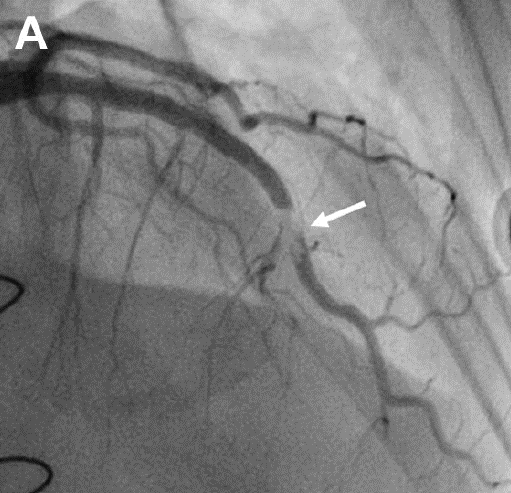

Experimentally, BioGlue Surgical Adhesive has been reported to induce inflammatory changes, anastomotic stenosis in coronary artery anastomoses, and coronary artery embolism.9-11,12 The mechanical properties demonstrate an increased stiffness compared to normal aortic tissue, which may promote pseudoaneurysm formation through augmented stress on the less compliant native aortic wall.13 The low viscosity of BioGlue Surgical Adhesive has been reported to promote leakage through anastomoses or needle holes.14 Furthermore, neurotoxicity has also been described as a result of the glutaraldehyde component. 9 In addition, coronary artery embolism as a result after acute type A aortic dissection repair has been reported (Figure 3).12

Figure 3. In a case report published in 2021, a patient experienced a coronary artery embolism following use of BioGlue Surgical Adhesive. (A) Mid-left anterior descending (LAD) artery filling defect representing a non-atherosclerotic blockage on coronary angiography. (B) Illustration of coronary embolism in the mid-LAD and right coronary artery due to BioGlue Surgical Adhesive.12